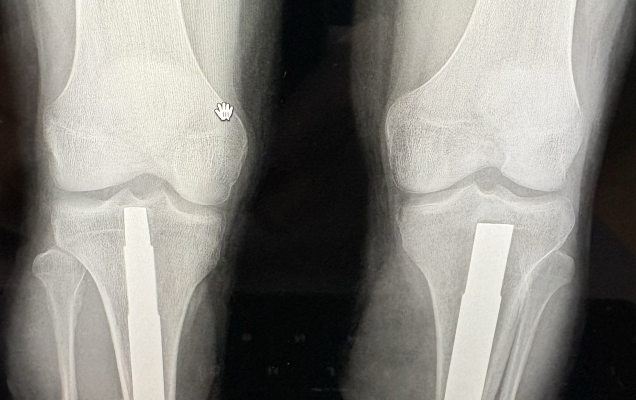

W Klinice Traumatologii i Ortopedii WIM-PIB przeprowadzono innowacyjny i rzadko wykonywany zabieg jednoczasowej osseointegracji obu podudzi u 19-letniego pacjenta po amputacji urazowej. To ważny krok naprzód w nowoczesnym leczeniu osób po amputacjach kończyn dolnych.

Osseointegracja polega na trwałym połączeniu implantu z kością, co umożliwia bezpośrednie mocowanie protezy bez konieczności stosowania tradycyjnego leja protezowego. Rozwiązanie to zapewnia pacjentom większy komfort użytkowania, lepszą kontrolę ruchu oraz wyraźną poprawę jakości życia. Przeprowadzona operacja była szczególnie wymagająca, ponieważ objęła obie kończyny jednocześnie. Jednoczasowe wykonanie zabiegu niesie jednak istotne korzyści – pozwala uniknąć drugiej hospitalizacji i kolejnego znieczulenia ogólnego, skraca całkowity czas leczenia oraz umożliwia prowadzenie symetrycznej rehabilitacji obu kończyn już od początku procesu usprawniania. Dzięki temu pacjent ma szansę szybciej powrócić do samodzielnego funkcjonowania.